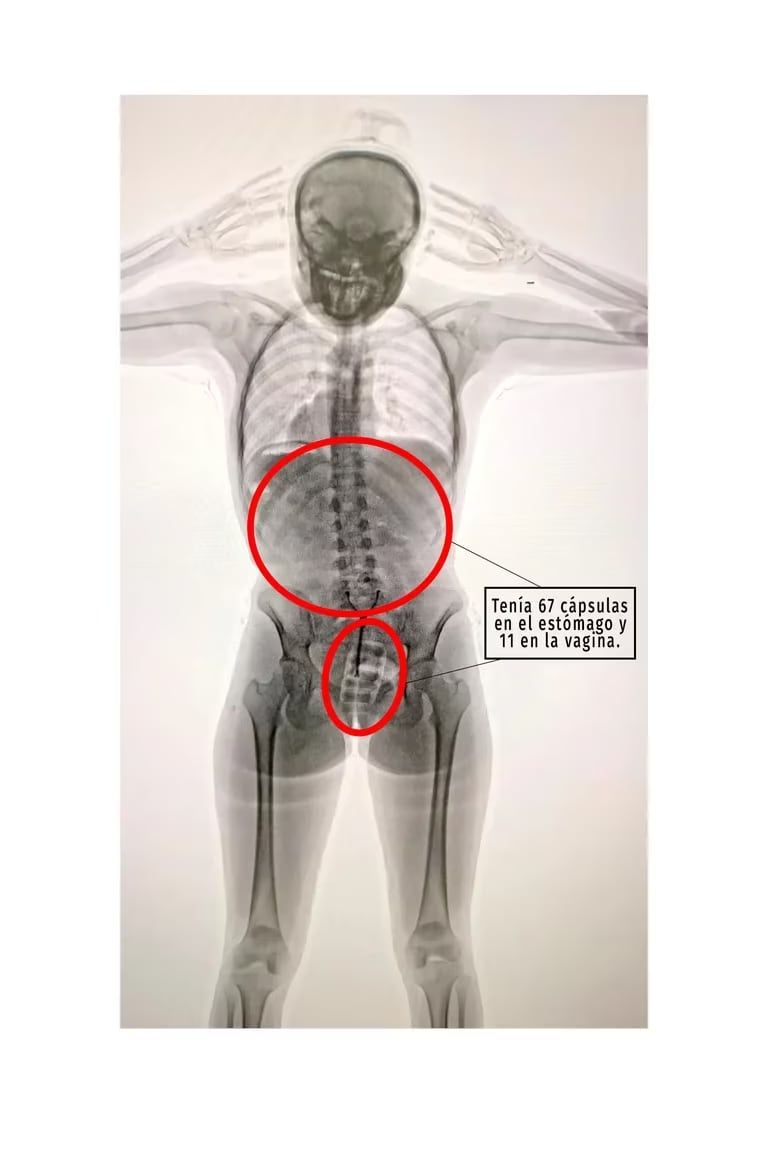

Allí se descubrió que la joven había ingerido 78 cápsulas de 10 gramos de cocaína cada una y las llevaba dentro de su cuerpo, por lo que de inmediato quedó en calidad de detenida y fue trasladada al Hospital Zonal General de Agudos Doctor Alberto Antranik Eurnekian, donde quedó internada.

Una fuente judicial explicó a Télam que, en el centro asistencial, “los médicos detectaron la presencia de elementos extraños introducidos en la zona vaginal y en el sistema digestivo”, por lo que fue sometida a un tratamiento para la evacuación total de todas las cápsulas.